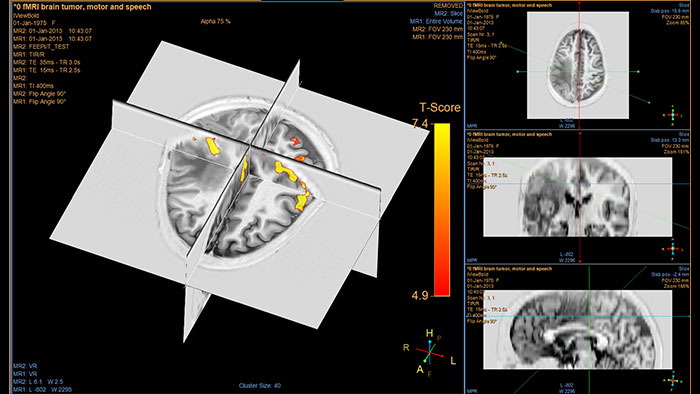

Analiza żywotności tkanki mózgowej

Aplikacja MR T2* (Neuro) Perfusion służy do oceny perfuzji mózgowej w diagnostyce udaru oraz obserwacji innych chorób. W przypadku ostrego udaru mózgu aplikacja ta umożliwia wizualizację i ilościową analizę rozbieżności w zakresie dyfuzji i perfuzji.